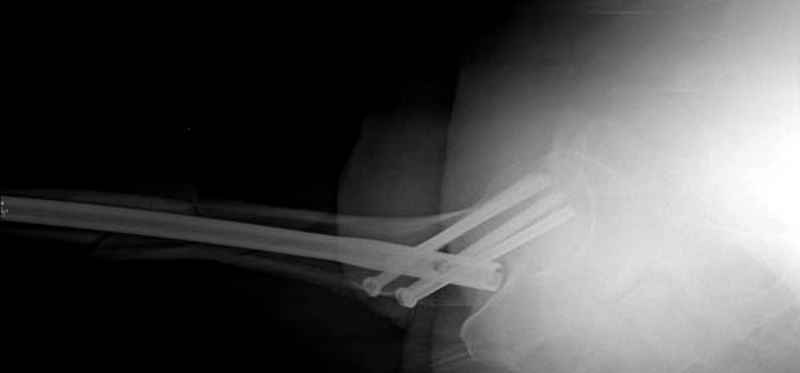

Учитывая, что случай ургентный, больной поступил вечером, не стали делать вытяжение и срочно провели операцию по фиксации перелома бедра антеградным штифтом Versa Nail от DePuy.

Для профилактики дальнейшего раскола в шейке предварительно во время проксимального рассверливания спереди и сзади провели временные спицы, которые в дальнейшем были заменены на шурупы (miss nail method)

Обычная спасательная фасциотомия для обычного больного в этом случае было бы приговором, поэтому несмотря на высокие цифры компартментального мониторинга больного оставили под наблюдением с обкладкой конечности льдом.